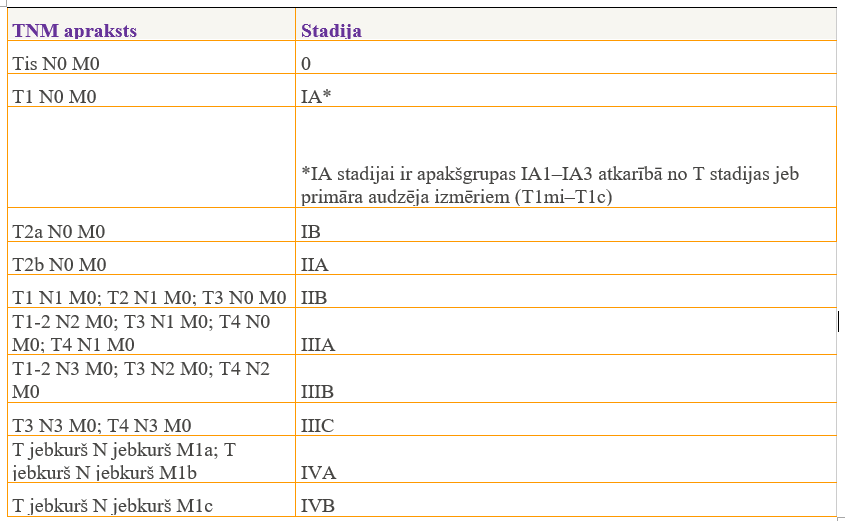

Šī tabula norāda TNM iedalījumu, kas specifisks tieši plaušu vēzim: